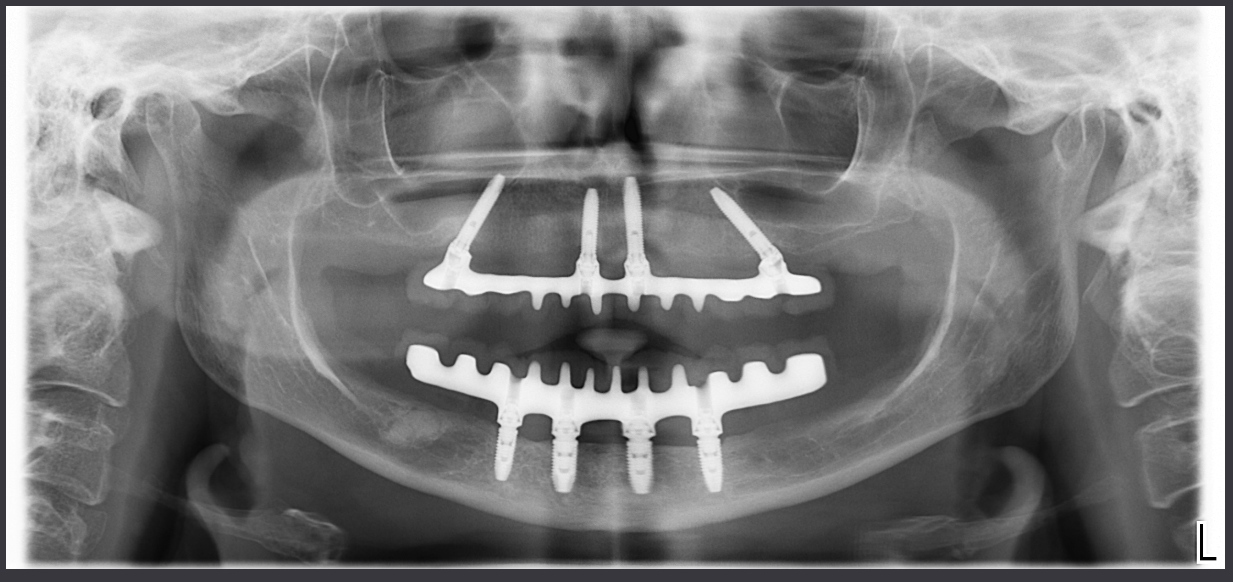

Cosa ho fatto io, invece con la mia paziente!?

Ti faccio vedere.

Eppure l’osso non c’era!!!! O almeno così aveva detto l’interpretazione rigida della simulazione al computer.

Questo è il controllo a un anno della mia paziente, un giorno ti mostrerò l’inferiore!